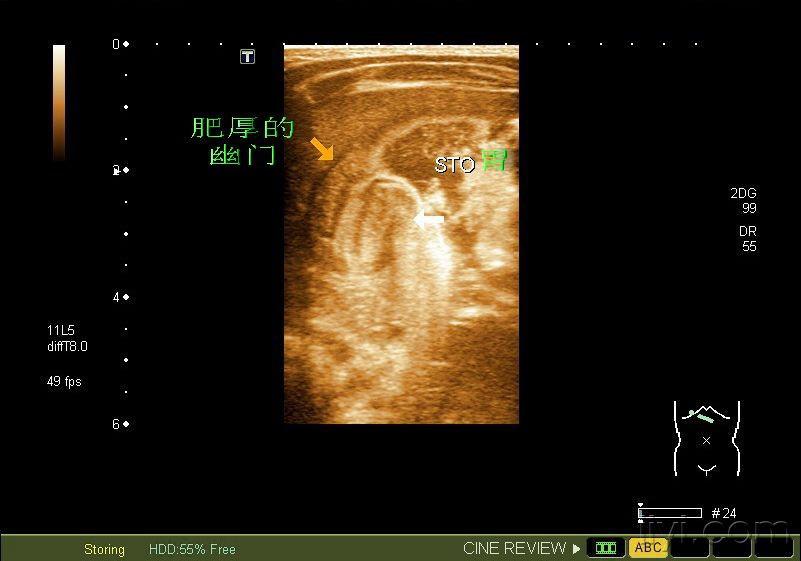

典型婴儿幽门梗阻

图片尺寸640x478